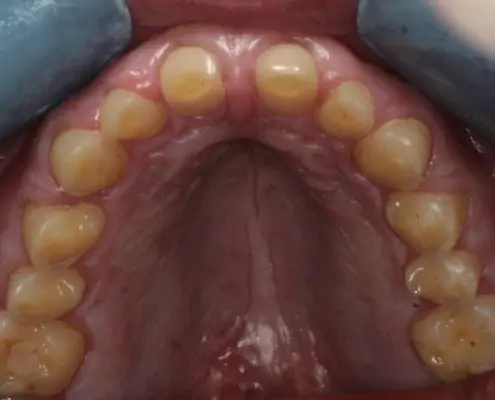

AvantAprès

Identifier les signes d’érosion dentaire

Les érosions dentaires peuvent être détectées lors d’un examen dentaire ou d’un détartrage. Des dents jaunies, une sensibilité accrue aux températures chaudes ou froides, ou des douleurs dentaires peuvent être des signes d’érosion dentaire.

Lorsque l’érosion est plus sévère il peut être indiqué d’effectuer un traitement de restauration  complète qui permet de rétablir l’esthétique et la fonction de mastication de vos dents.

Les médecins dentistes de D1 Dental Concept sont expérimentés dans le diagnostic et le traitement des érosions dentaires.

Nous utilisons particulièrement les dernières techniques de dentisterie micro invasive permettant de restaurer de telles lésions en préservant un maximum de matière dentaire résiduelle.